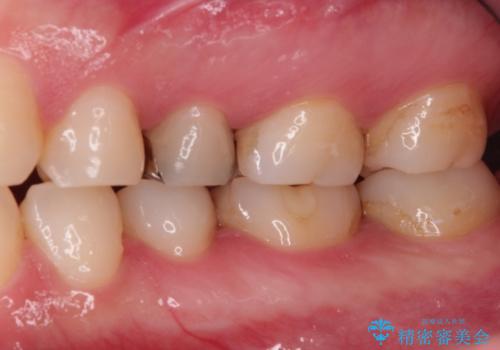

古い材料を除去すると中で虫歯が進行していたため、顕微鏡下で虫歯を除去した後セラミックインレー、PGAインレーにて修復治療を行いました。

セラミック治療の注意事項(リスク・副作用など)

- 天然歯を削ります

- 硬い素材は天然歯を傷つけてしまう場合があります

- かみ合わせや歯ぎしりが強すぎる方はセラミックが割れてしまう可能性があります

- 自費診療(保険適用外治療)となります